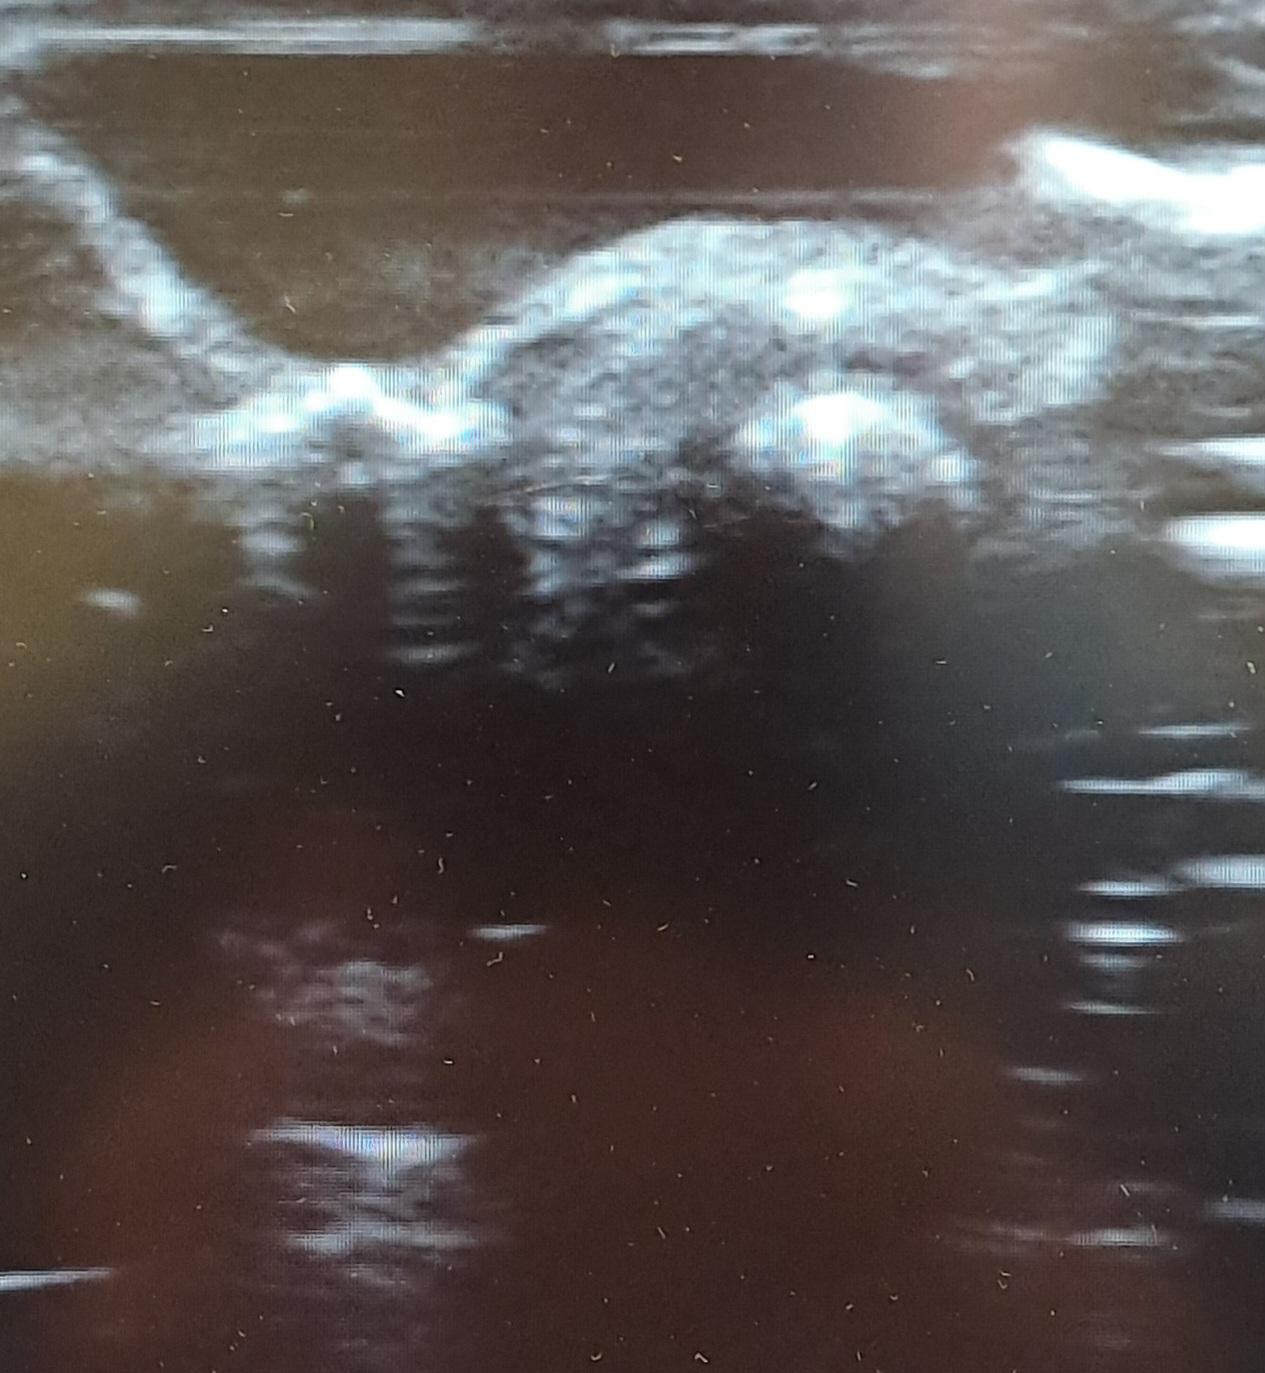

Se realiza ecografía clínica utilizando un guante lleno de agua para valoración cutánea.

En la ecografía clínica se objetiva aumento de tamaño de la piel de aspecto nodular en región superior de la dermis objetivando una línea hiperecogénica sin sombra acústica posterior en región central de la lesión.